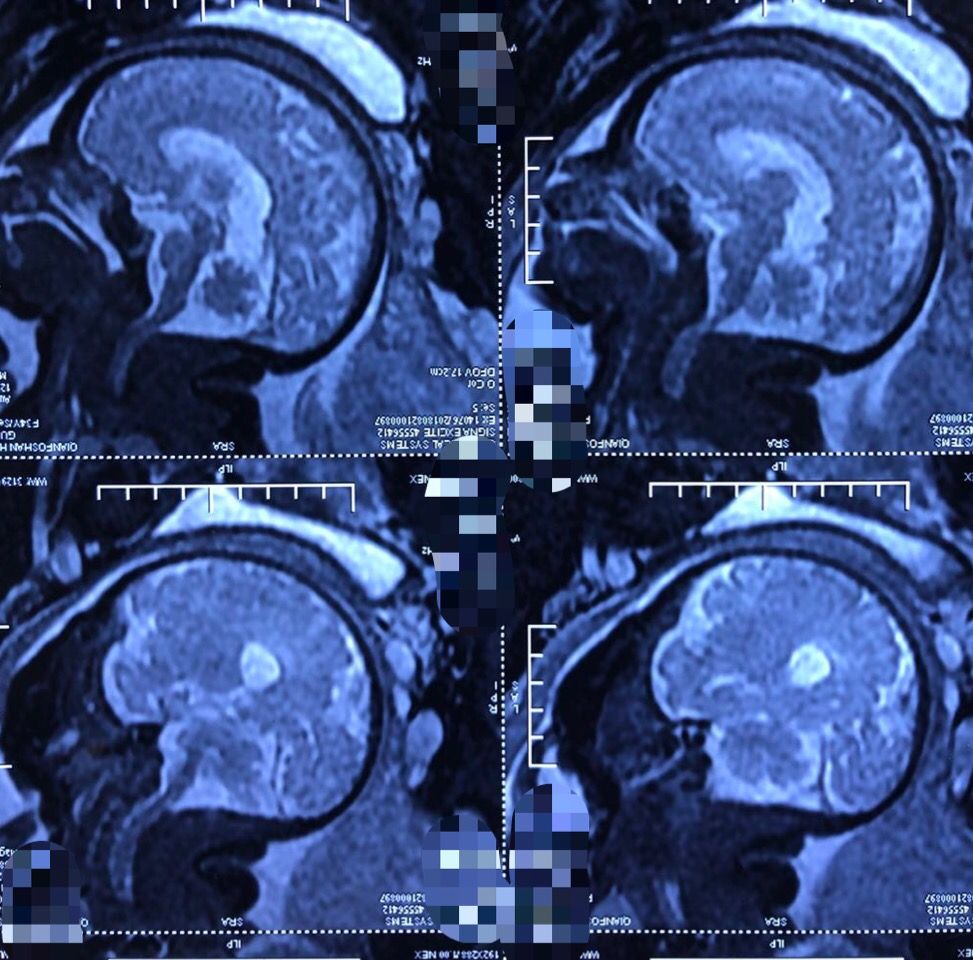

孕40周胎儿核磁共振

孕40周胎儿核磁共振